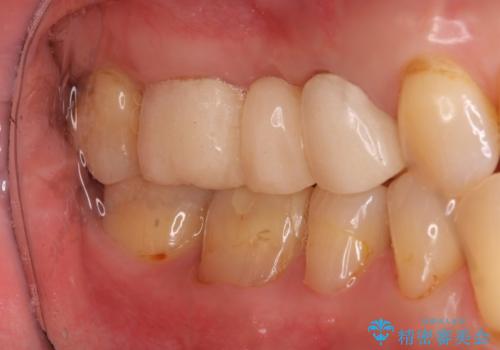

- 他院でブリッジの仮歯を入れたが、外れやすいため転院を希望された患者様です。

支台歯の形が角度が大きくついた形に形成してあり、外れやすい形になっていたため修正してから歯型をとりました。

- 36.3万円(ジルコニアクラウン10万円x3本)費用は治療当時の料金となります